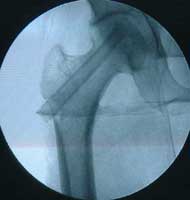

股骨头缺血性坏死MRI显示坏死区          微创手术方法,采用隧道减压刮除死骨

BMP植入,异体骨支撑,恢复形态     手术后24个月X线片,关节塌陷未加重,关节功能良好,无疼痛